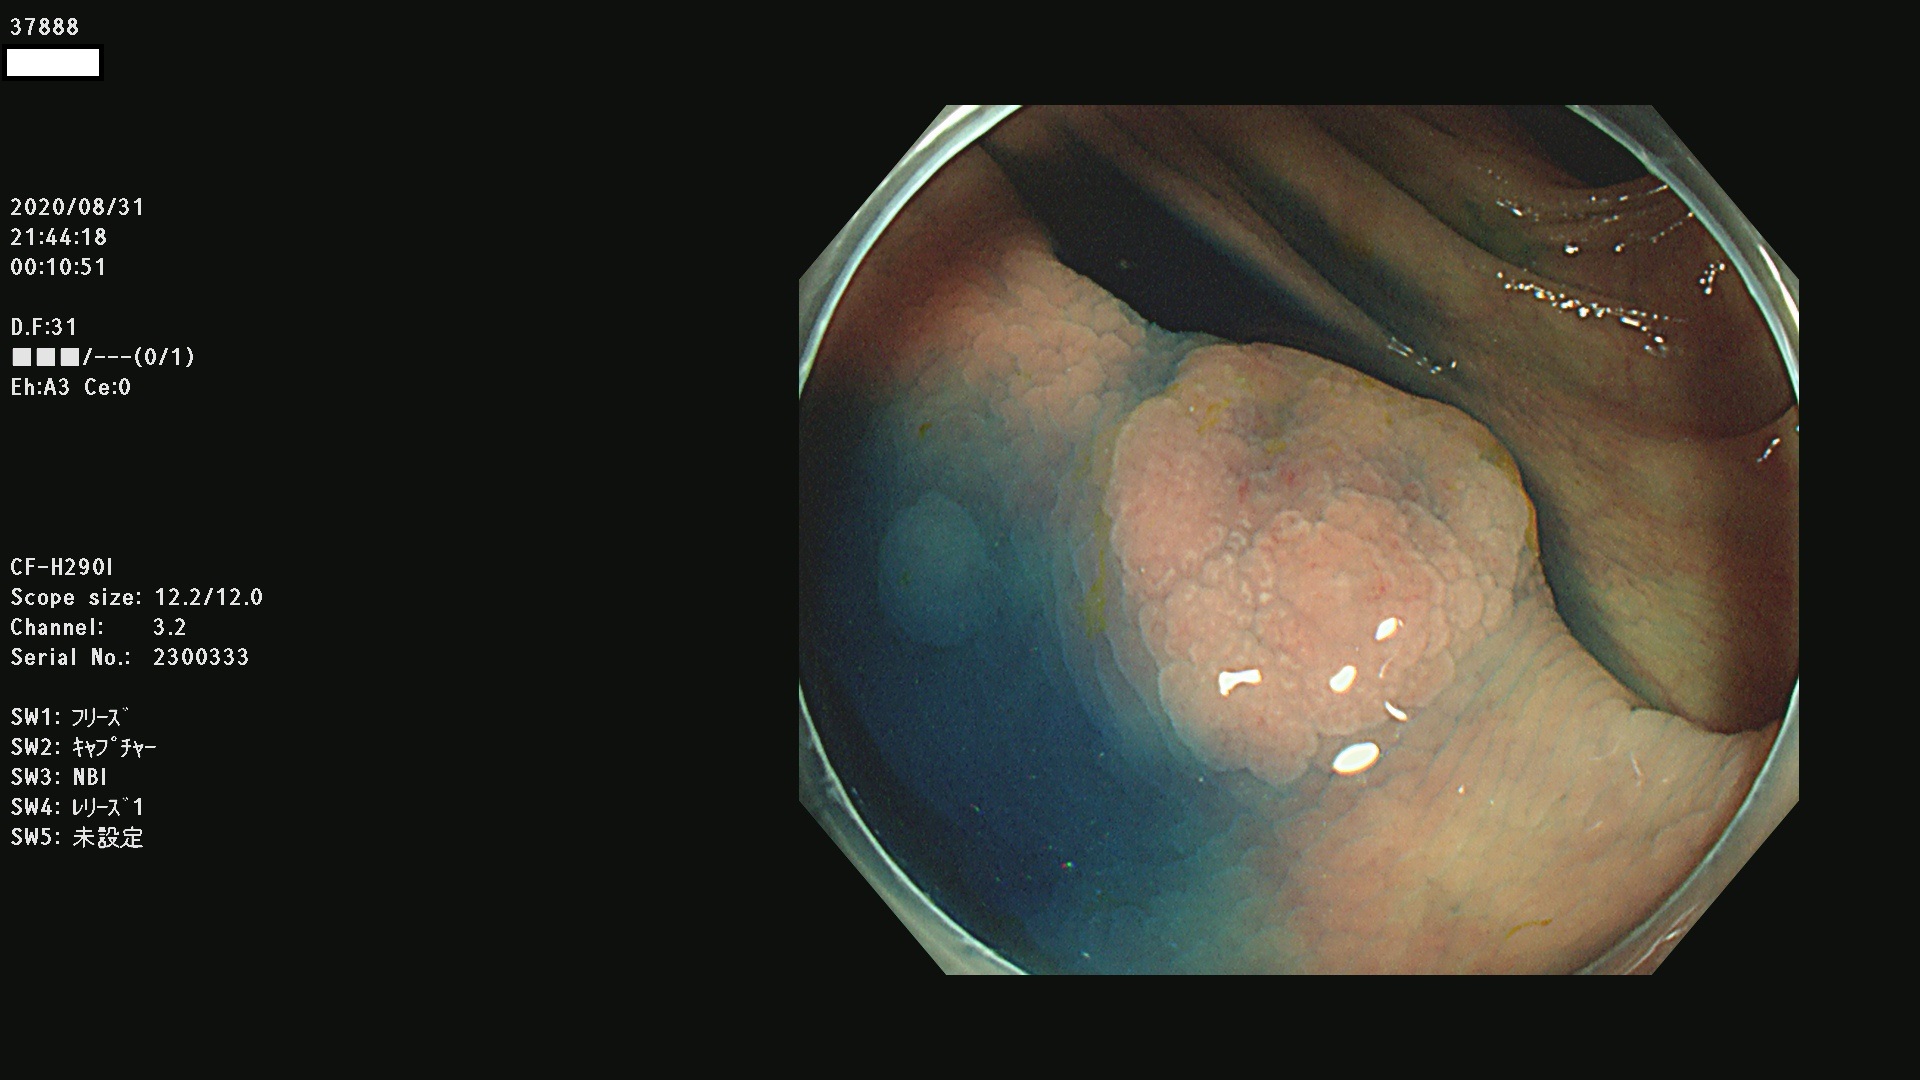

腺腫発見率 75 % (カルテ番号 37800〜37899の100名の方の検査結果で集計)大腸癌検診最新情報

以下のカルテ番号の方に腺腫(Adenoma,Group3〜5)が見つかりました(集計法)

37800(SSAPのみ) 37801 37802 37803 37804 37805 37806 37807 37808 37809(SSAPのみ) 37810 37811 37812 37813 37814 37815 37817 37818 37819 37820 37821 37822 37824 37825 37826 37827 37828 37829 37832 37833 37836 37837(SSAPのみ) 37839 37840 37842 37844 37845(SSAPのみ) 37847 37849 37850 37851 37852 37853(SSAPのみ) 37855 37856 37857 37860 37861 37862 37863 37864 37867 37868 37871 37874 37876 37877 37879 37880 37881 37882 37883 37886 37887 37888 37889 37890 37891 37892 37893 37894 37896 37897 37898 37899

発見困難で危険性の高い平坦型病変(上記100名より抽出) ![]()